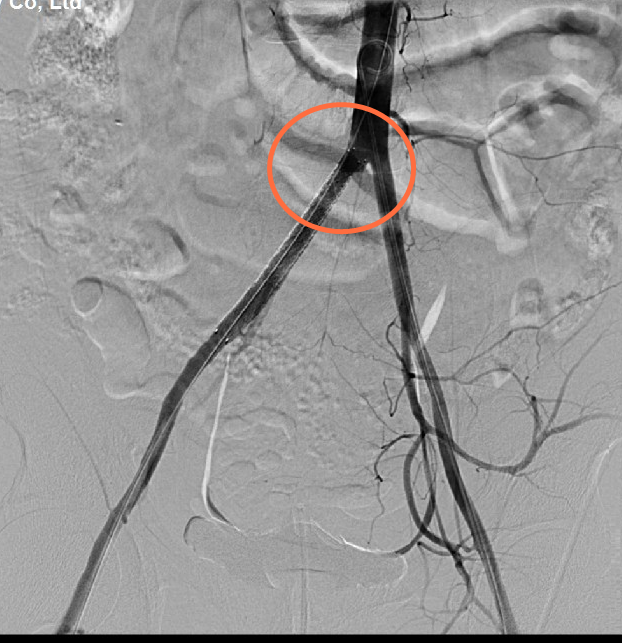

术前造影右髂总动脉与腹主动脉交界处血管壁损伤

先行介入右侧髂动脉支架内隔绝术

来到市二院后,经过初步检查,吕先生被碾严重,肋骨骨折,腹壁肌肉断裂,肠管破裂,以及髋部、右臀部皮肤破裂受伤出血。CT检查中,还发现一个非常棘手的问题,右侧髂动脉与腹主动脉交界处有血肿,一旦破裂,就会有生命危险时间就是生命,普外一病区刘利亭主任当机立断,立即带领团队医护人员进入导管室,为吕先生实施侧髂动脉支架内隔绝术。在医护人员的不懈努力下,手术顺利完成。虽然拆掉了血肿这个最危险的“雷”,但吕先生的情况依然不容乐观。